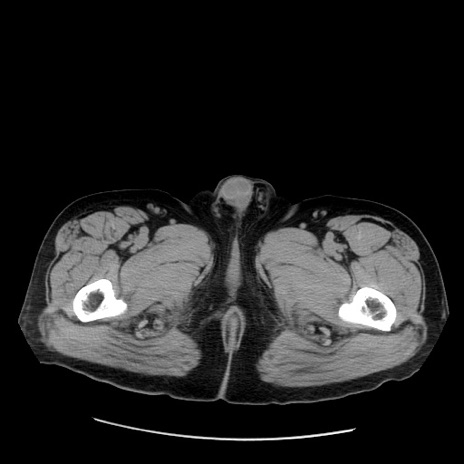

症例20(横断像)

【症例】 60歳代男性

【主訴】 腹部膨満、嘔吐

【現病歴】5日前頃より倦怠感を認め食事量減少し4日前の朝嘔吐、食事摂取困難となった。 3日前近医受診し点滴施行され整腸剤などを処方された。 当日他院を受診し、腹部膨満著明、炎症反応の上昇(CRP10.8、WBC11200)あり、紹介受診となる。

【身体所見】 意識JCS1 受け答えがはっきりしないBP 111/57mHg、 P 67bpm、、BT35.2°C、SpO2 97%(RA)、 腹部:膨隆、打診で鼓音あり、全体的に圧痛有り、腸蠕動音(-)、反跳痛ははっきりせず。

【データ】WBC 11400、CRP 14.20